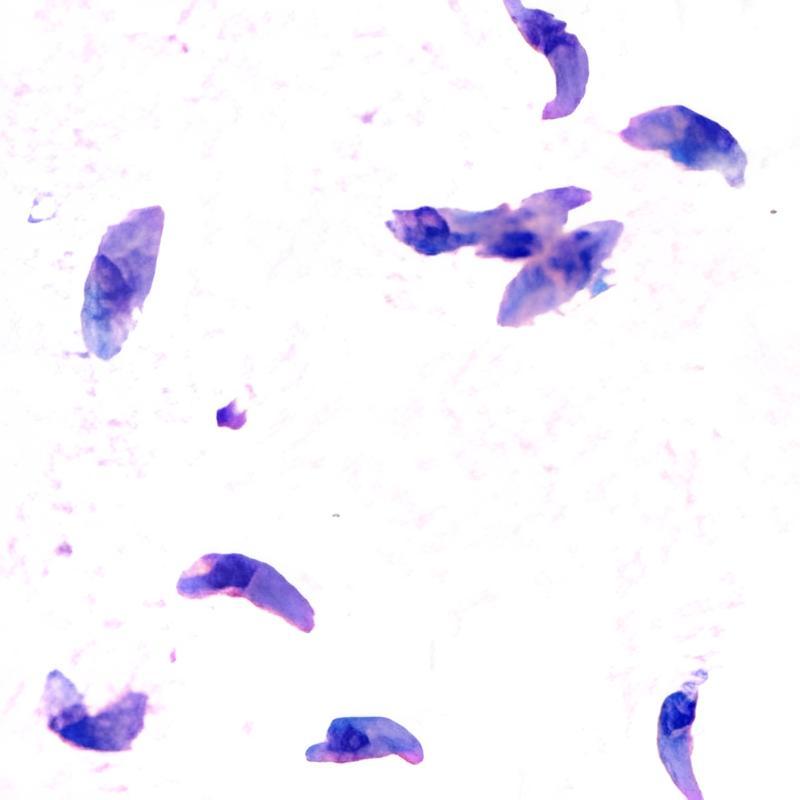

Toxoplasma gondii вызывает болезнь токсоплазмоз. Обычно ее связывают с кошками, ведь именно они являются основными «хозяевами» паразита. Но в Йеллоустоне у этой истории оказались другие герои — волки.

Получается, что вожаком волчьей стаи может стать не обязательно самый сильный и умный волк, но и волк, который болен токсоплазмозом. Именно микроскопический внутриклеточный паразит превращает осторожного хищника в смелого одиночку, тем самым открывая ему дорогу на «иерархическую вершину» в стае.